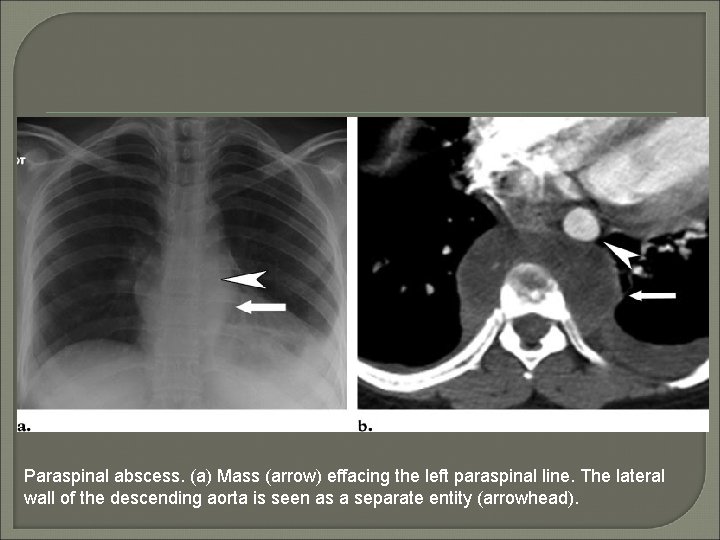

The paraspinal lines: Interface between lung and the pleural reflections over the vertebral bodies. The left paraspinal line runs parallel to the lateral margin of the vertebral bodies and can lie anywhere medial to the lateral wall of the descending aorta (seen due to the interface between the lateral aortic margin and the lung). The right paraspinal line lies within a few millimeters of the vertebrae.

Paraspinal abscess. (a) Mass (arrow) effacing the left paraspinal line. The lateral wall of the descending aorta is seen as a separate entity (arrowhead).